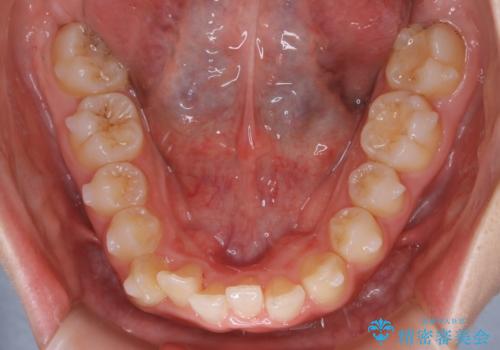

【非抜歯】すきっ歯と噛み合わせの治療

- 上の前歯のすきっ歯と下の前歯のガタつきを主訴にご来院されました。

噛み合わせの改善も同時に進めつつ、主訴の部分も効率的に治していくためマウスピース装置でゴムかけを行いながら治療を進めていきました。